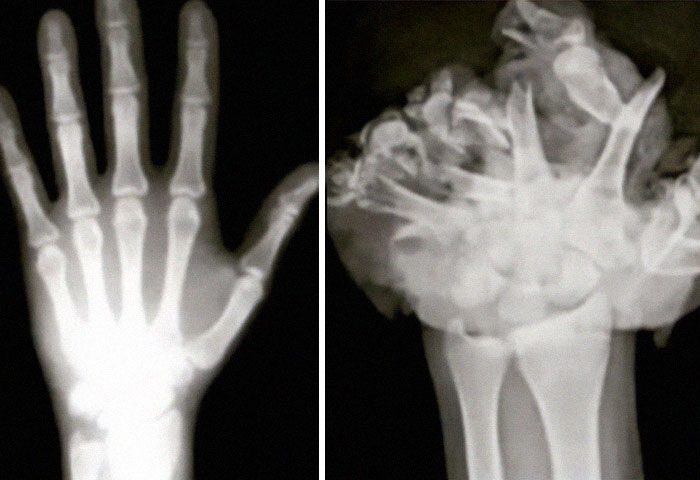

#10 Normal Hand / Hand After Firework Explosion

Image source: Dressa1996